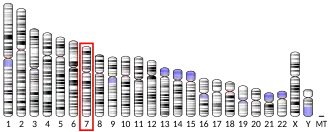

- Schanen NC, Scherer SW, Tsui LC, Francke U (1997). "Assignment of the 5-hydroxytryptamine (serotonin) receptor 5A gene (HTR5A) to human chromosome band 7q36.1". Cytogenetics and Cell Genetics. 72 (2–3): 187–188. doi:10.1159/000134184. hdl:10722/42533. PMID 8978771.